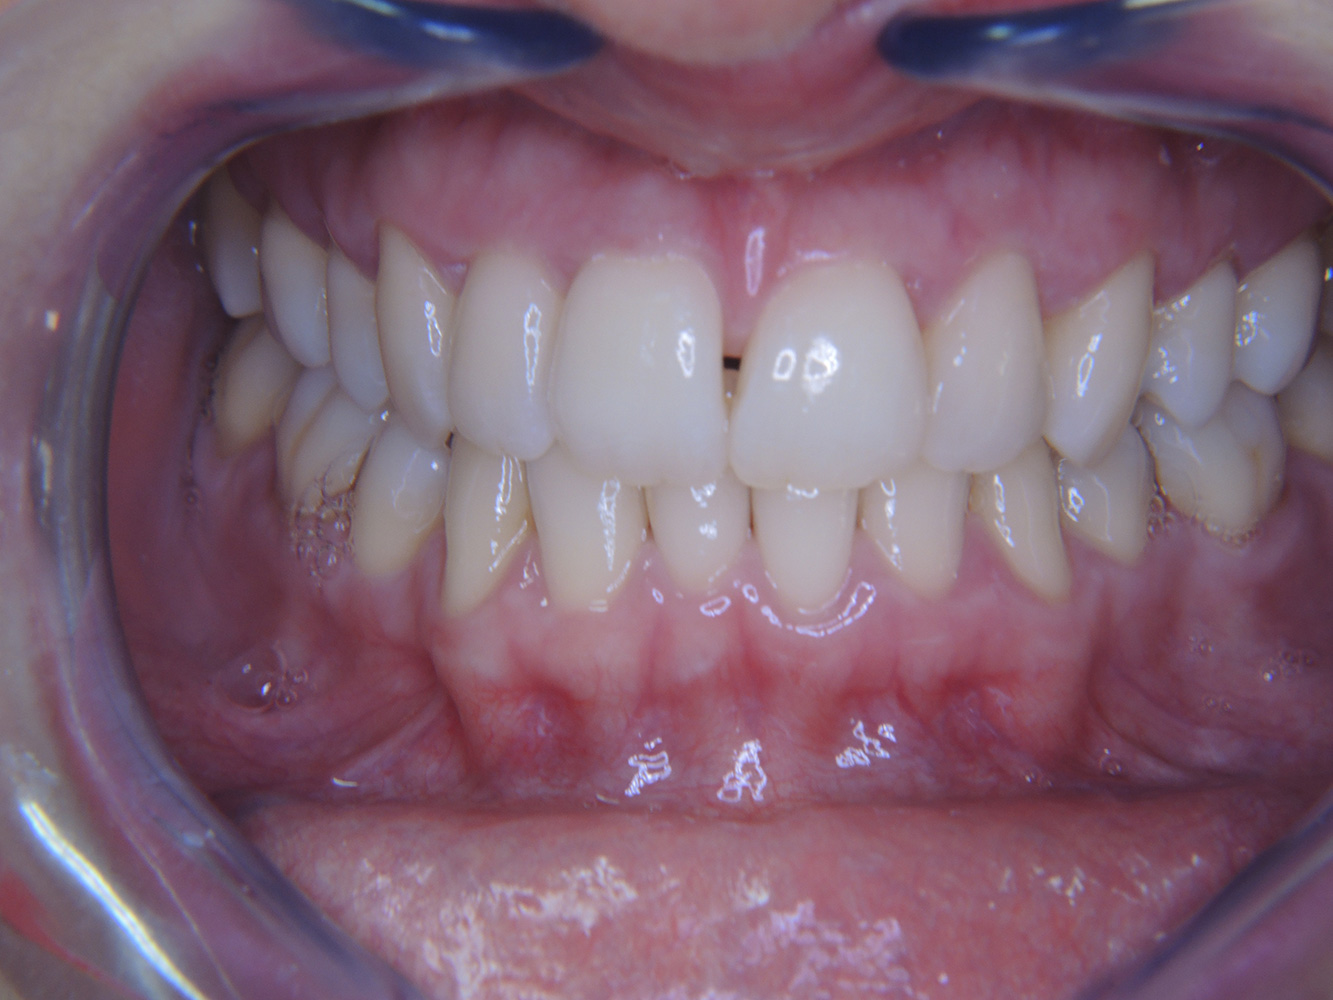

Patient cases according to IPC

The following case studies* serve to illustrate the interaction between the need and risk factors defined for the IPC, as well as the effects of individual factors.

The (orally) healthy patient with implants

In the medical history, the 55-year-old patient states that he has no systemic disease and is not taking any medication. The patient’s lifestyle is similarly unremarkable. The patient has a few tooth restorations and two implants (2nd and 4th quadrants). On the basis of current findings, gingivitis is identified in an otherwise stable periodontal condition on the reduced periodontium (stage III, grade A). more